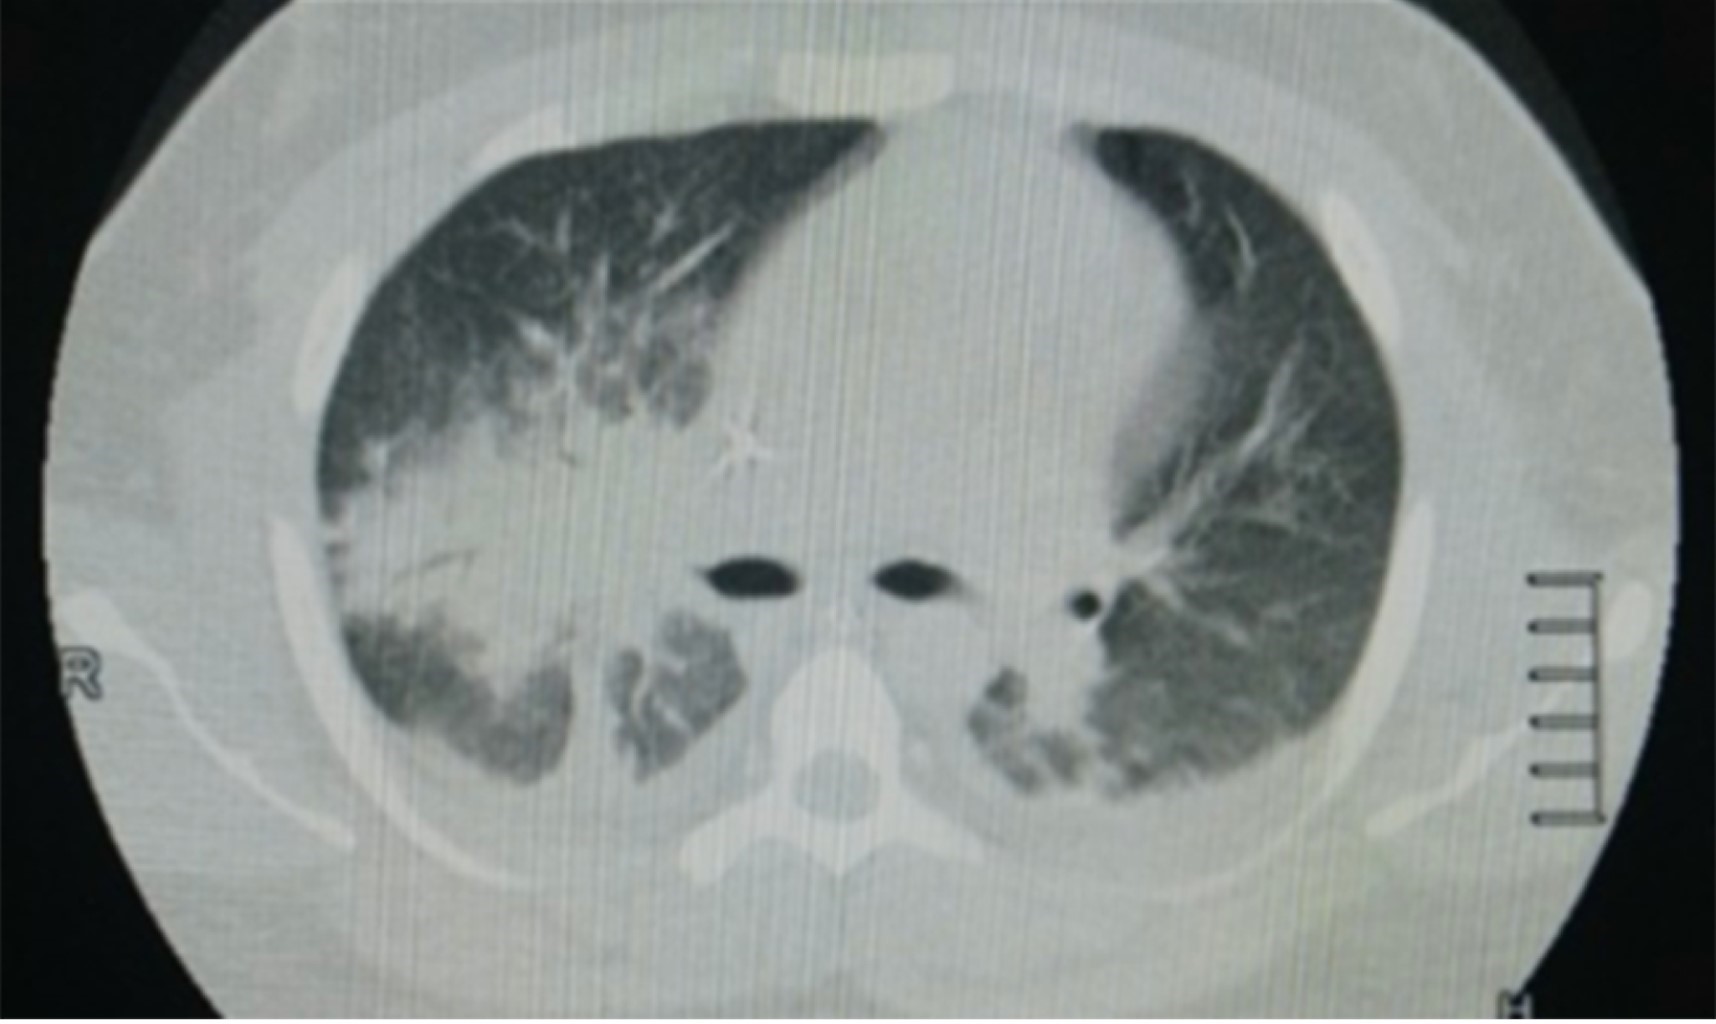

We present a clinical case of a young male in the second decade of life who presented septic shock due to enterobacteria with extended resistance isolated in rectal swab requiring early sepsis campaign guidelines. Had severe pulmonary injury and markers of fibrinolytic activity, pulmonary perfusion is performed by nuclear medicine documenting pulmonary thromboembolism secondary to antithrombin III deficiency and Leiden factor V. It evolves favorably with recovery of ventilatory mechanics tolerating release of mechanical ventilation without compromise of oxygenation or ventilation so it is decided to transfer to internal medicine and hematology.

Figure 1